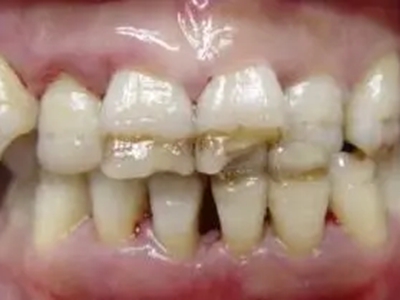

牙釉质发育不全牙表面上有坑图

牙釉质发育不全发展到严重时,导致牙釉质表面缺损,表现为带状、窝状的褐色凹坑,容易积存食物残渣诱发龋齿,表现为牙齿边上出现深褐色小洞。